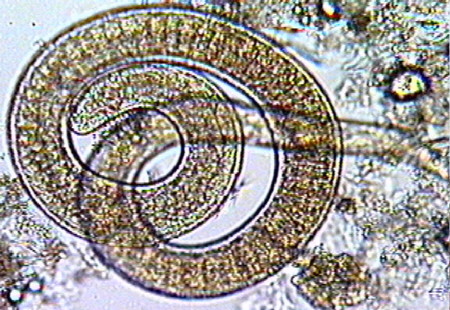

旋毛形线虫